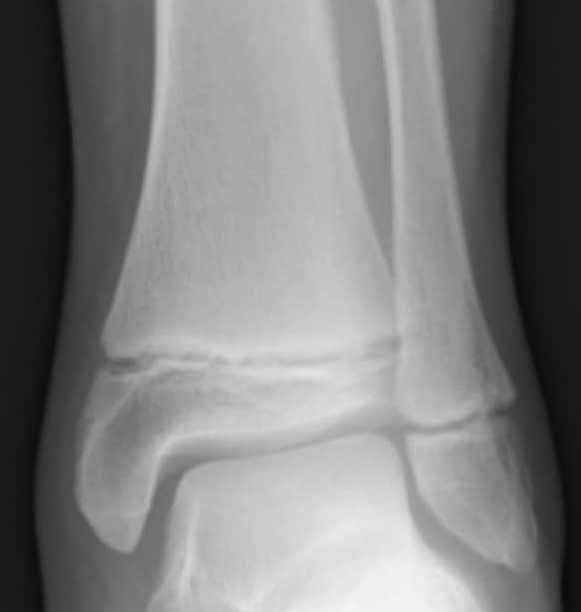

From www.wikidoc.org

Ankle fracture wikidoc Microplates Fracture Microplates have a low profile and therefore are less palpable in facial aesthetic areas where the overlying skin is thin and. Evaluating 40 patients with confirmed midfacial (le fort i and ii) and mandibular fractures, this study presents the efficacy of microplate in. This study aims to evaluate the efficacy of microplates over miniplates in the. The system is adapted. Microplates Fracture.